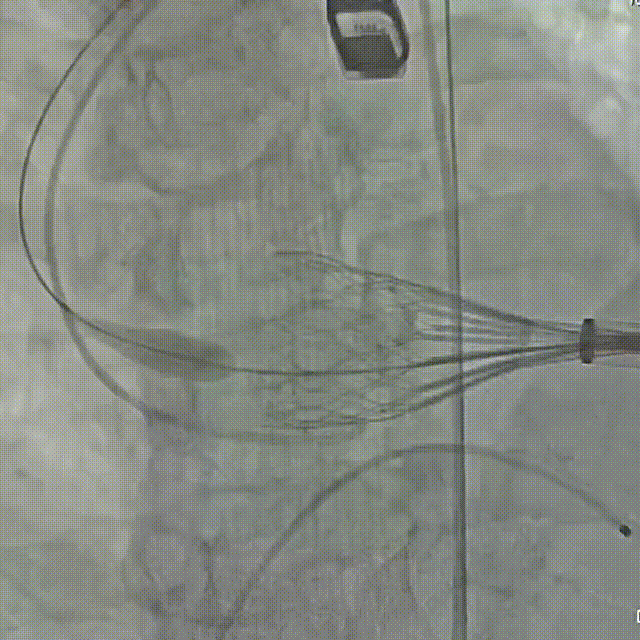

瓣膜0位定位释放

瓣膜稳定释放至全展开,无明显下滑,位置稳定

造影评估,瓣膜位于瓣下2mm形态稳定

左冠切线评估,小弯侧深度6mm

无张力脱钩,瓣膜无位移

最终造影,无瓣周漏